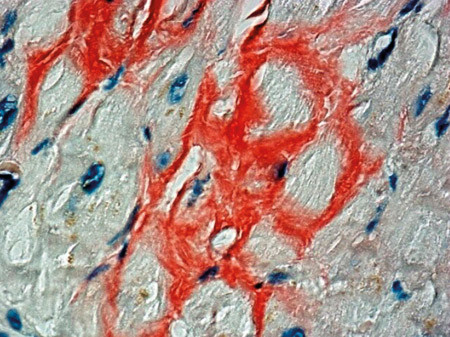

Transvenøs biopsi av endomyokard viste avleiring av amyloid (fig 2), der immunohistokjemisk fremstilling avdekket nedslag av transtyretin (prealbumin) (fig 3).

Amyloidose er en tilstand karakterisert ved nedslag av monomorft proteinmateriale i ett eller flere vev. Dette materialet gir et karakteristisk «eplegrønt» skimmer når det farges med kongorødt og betraktes i polarisert lys. Flere naturlig forekommende og muterte proteiner har evnen til å danne amyloid. Etter molekylærbiologiske fremskritt kan man nå skille mellom en rekke typer amyloidose ut fra hvilket protein som felles ut (6). De viktigste systemiske formene for amyloidose er amyloid lettkjede (AL)-amyloidose (tidligere kalt «primær» amyloidose), forårsaket av nedslag av lette kjeder ved monoklonal plasmacelleproliferasjon, og amyloid A-protein (AA)-amyloidose («sekundær» amyloidose). Ved sistnevnte er det nedslag av et leversyntetisert akuttfaseprotein ved langvarig inflammatorisk tilstand (6).

Kardial amyloidose medfører ofte EKG-forandringer, mest typisk ses små elektriske amplituder i standardavledningene (low voltage). Funnet er imidlertid ikke patognomonisk (9) og fantes ikke hos vår pasient. Ekkokardiografisk ses fortykkelse av myokard med typisk ekkogenisitet og restriktivt fyllingsmønster (10). For sikkert å kunne stille diagnosen kreves imidlertid biopsi – ved systemisk sykdom kan biopsi tas fra rectum eller abdominalt fettvev. Imidlertid er sensitiviteten ved biopsi i ekstrakardialt vev lav ved ATTR-amyloidose (9).